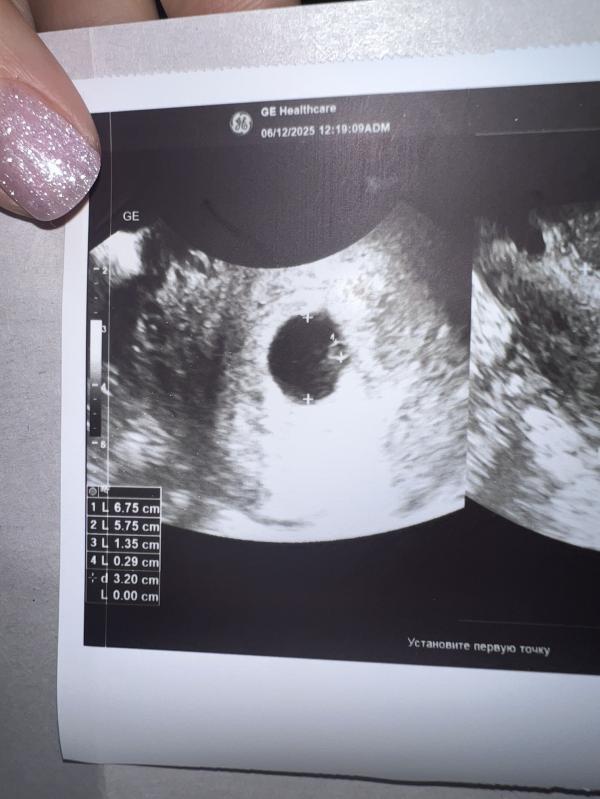

5 недель 5 дней

Подтвердили маточную беременность, увидели эмбриончик 🙏🏻 сердцебиения еще нет ☹️ через недельку переделаю